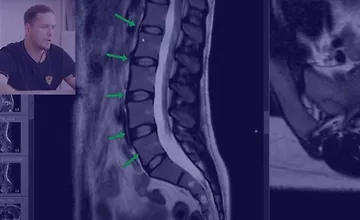

Как читать МРТ поясницы

На множестве примеров изображений вы научитесь распознавать грыжу, протрузию, стеноз позвоночного канала, компрессию нервных корешков, жировую дегенерацию мышц и спазмы мышц при наличии грыжи. Вы узнаете, как возникает поясничный прострел и многое другое. Регулярно анализируя МРТ своих пациентов и сопоставляя полученные данные с их жалобами, вы сможете все лучше понимать причины их болевых ощущений.